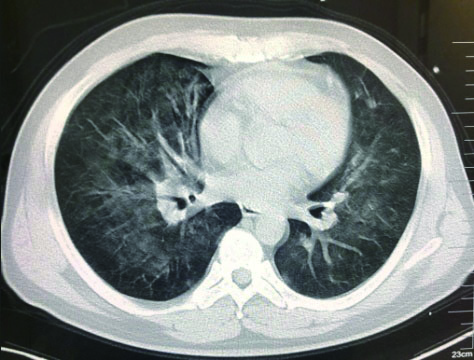

1.2 临床表现和检查患者初期有咳嗽症状,但未在意,患者回家24 h后咳嗽症状加重,伴胸闷气喘,全身大汗淋漓,家属立即将其送至本院急诊,为进一步诊治拟“有机氟中毒”收住入院。入院时体检:神志清楚,T:36.5℃,R: 57次/min,BP: 146/71 mmHg,胸廓对称无畸形,呼吸急促,听诊双肺呼吸音清晰,可闻及大量湿性啰音,心率112次/min,心律齐,心音正常,各瓣膜听诊区未闻及病理性杂音及心包摩擦音,四肢关节正常,双下肢无水肿,深浅生理反射正常,病理反射阴性,脑膜刺激征阴性。辅助检查:白细胞计数10.45×109/L,中性粒细胞91.9%;C-反应蛋白14.81 mg/L, 无创机械通气支持下血气分析pH7.28,PCO2 50 mmHg, PO2 57 mmHg, Lac 3.0 mmol/L(FiO2 50%),为Ⅱ型呼吸衰竭,给予无创呼吸机辅助呼吸、激素冲击、解痉平喘等抢救治疗。急诊胸部CT检查提示:两肺散在斑片状模糊影,密度不均,边界不清(图 1),进ICU床边胸片提示:两肺散在斑片状模糊影(图 2)。根据GBZ5—2016《职业性氟及其无机化合物中毒的诊断》的诊断标准,该患者诊断为职业性急性重度有机氟中毒。

| 图 2 3月10日胸部X线 |